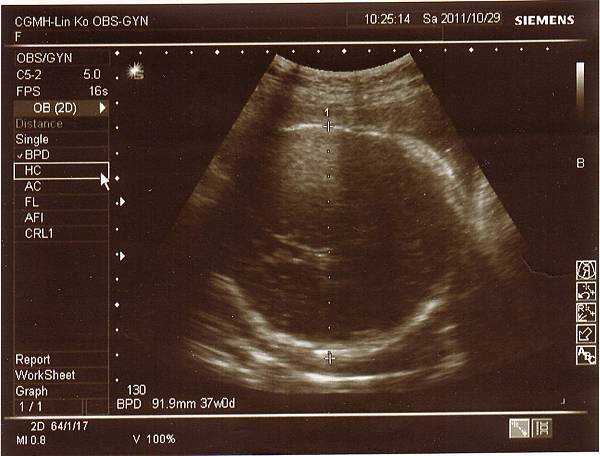

其實以預產期來算已經39週了,兔寶妹仍舊乖乖地待在肚子裡,

希望她可以到11月再出生,今天除了例行性產檢外,

1029-1.jpg